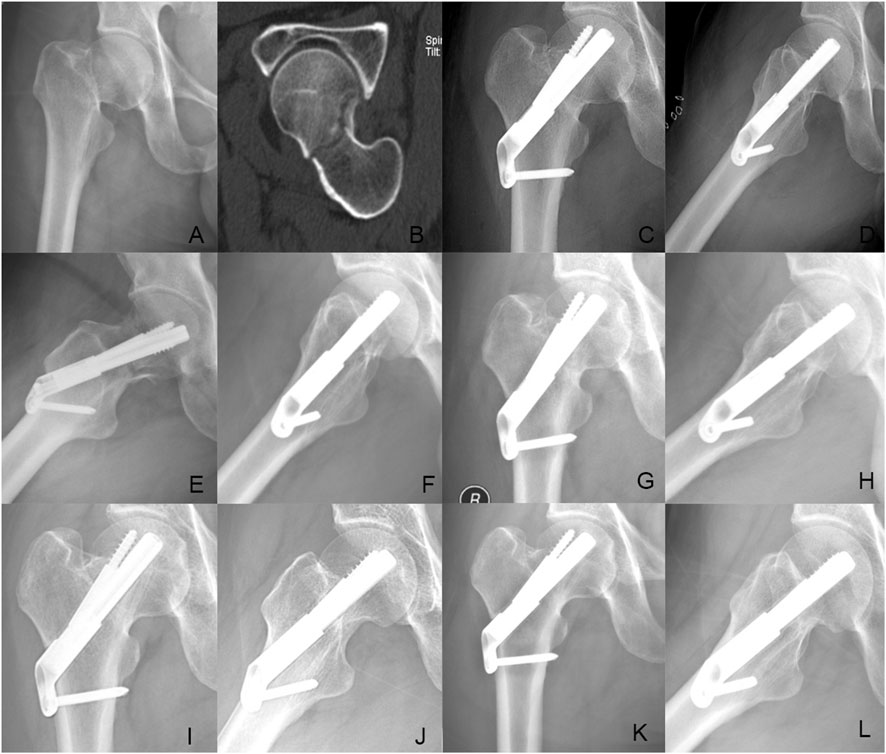

Background The purpose of this study was to explore the biomechanical property and clinical efficacy of femoral neck system (FNS) with an additional cannulated screws (CS) in the treatment of unstable femoral neck fracture (FNFs) with comminuted posteromedial cortex. Methods Firstly, we developed a model of Pauwels type III FNF with comminuted posteromedial cortex for the finite element analysis (FEA). Two experimental models were set up: the FNS model and the FNS+CS model. The von Mises stress on the proximal femur, implant and the total displacement of the device components were evaluated for both FNS and FNS+CS models. Secondly, we retrospectively included the cases of vertical FNFs with comminuted posteromedial cortex by FNS or FNS+CS fixation in our hospital from January 2020 to December 2023. In this study, demographic information, femoral neck shortening, Harris score of hip joint function, and postoperative complications were collected and compared. Results The FEA results showed similar peak von Mises stress of the implant in two models and the additional CS could share the stress concentration with the FNS in the FNS+CS model. In terms of proximal femur, the maximum von Mises stress of the FNS model increased by 15.43% when compared with the FNS+CS model, and the magnitude of these two models were 83.02MPa and 71.92 MPa, respectively. Furthermore, the maximum displacement in the FNS+CS model was much smaller than that in the FNS model. Clinically, the femoral neck shortening distance was significantly longer in the FNS group (5.62±3.32 mm) than that in the FNS+CS group (3.49±2.01 mm) (p = 0.027). Furthermore, the incidence of moderate to severe shortening (≥ 5 mm) was significantly higher in the FNS group compared with the FNS+CS group (p = 0.039). Moreover, the patients in the FNS+CS group had a higher Harris score than patients in the FNS group (91.97 vs. 88.56, p = 0.003). Conclusions Compared to the FNS alone, the FEA results showed that the FNS+CS had better biomechanical properties and the clinical results showed that the FNS+CS had a shorter femoral neck shortening and higher Harris score in treating unstable FNFs with comminuted posteromedial cortex.